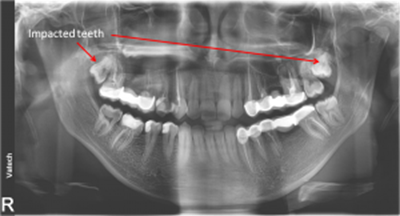

Digital x-rays can be used to diagnose:

- Impacted teeth